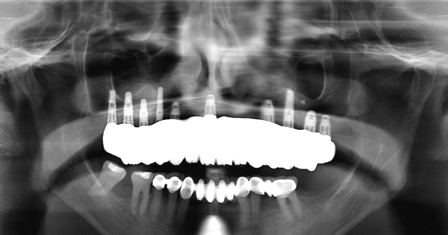

Fig 7. Preoperative panoramic radiograph. Note decay of supporting teeth.

Figure 7

Fig 9. CT guided surgery planning. Ten implants were planned, including a maxillary anterior implant to be placed in the anterior nasal spine.

Figure 9